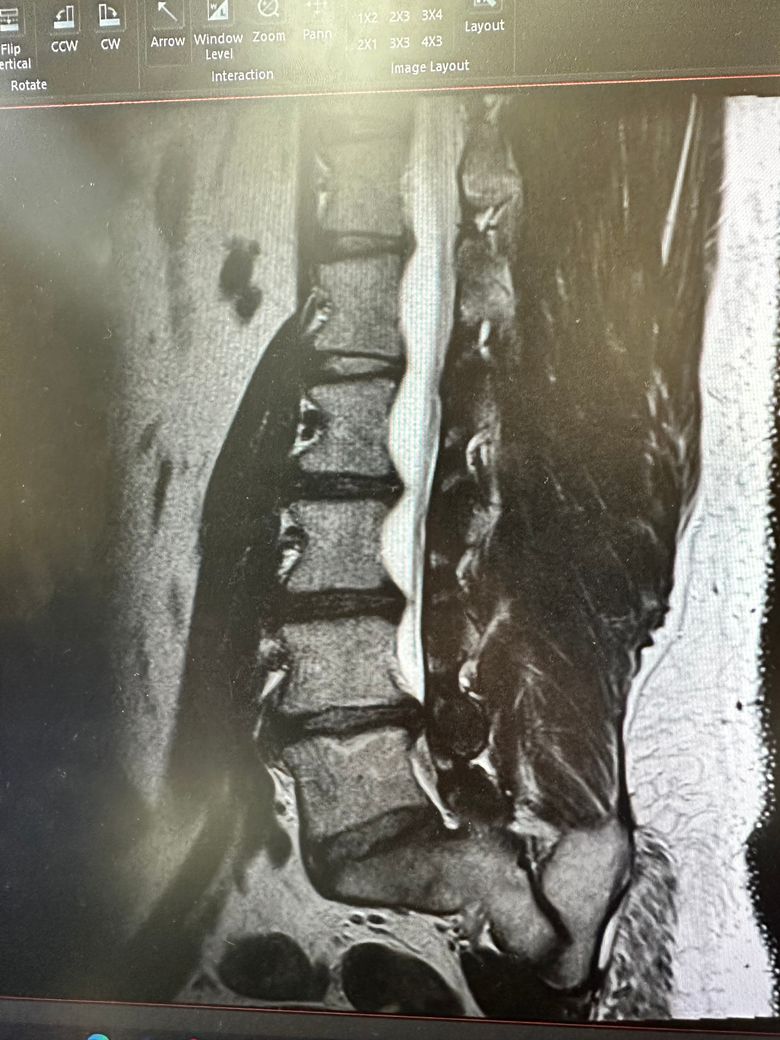

허리디스크 4번5번 돌출 심함 신경 누름

데스크 튀어 나와있어서 신경을 눌러 허리 통증및

저림 증상이 좀 있으며 걷기시 왼쪽 햄스트링 엉치쪽

통쯩이 심함 수술 권유 받았으나 다른 방안이 없울지..

말씀하신 내용 토대로만해서 답해드리자면 허리디스크 4번, 5번이 심하게 돌출되어 신경을 누르고 있는 상황이라면, 수술을 고려하기 전에 여러 비수술적 치료 방법을 시도해 볼 수 있습니다. 우선 물리치료, 약물치료, 체외충격파치료, 경막외 스테로이드 주사 등이 도움이 될 수 있구요